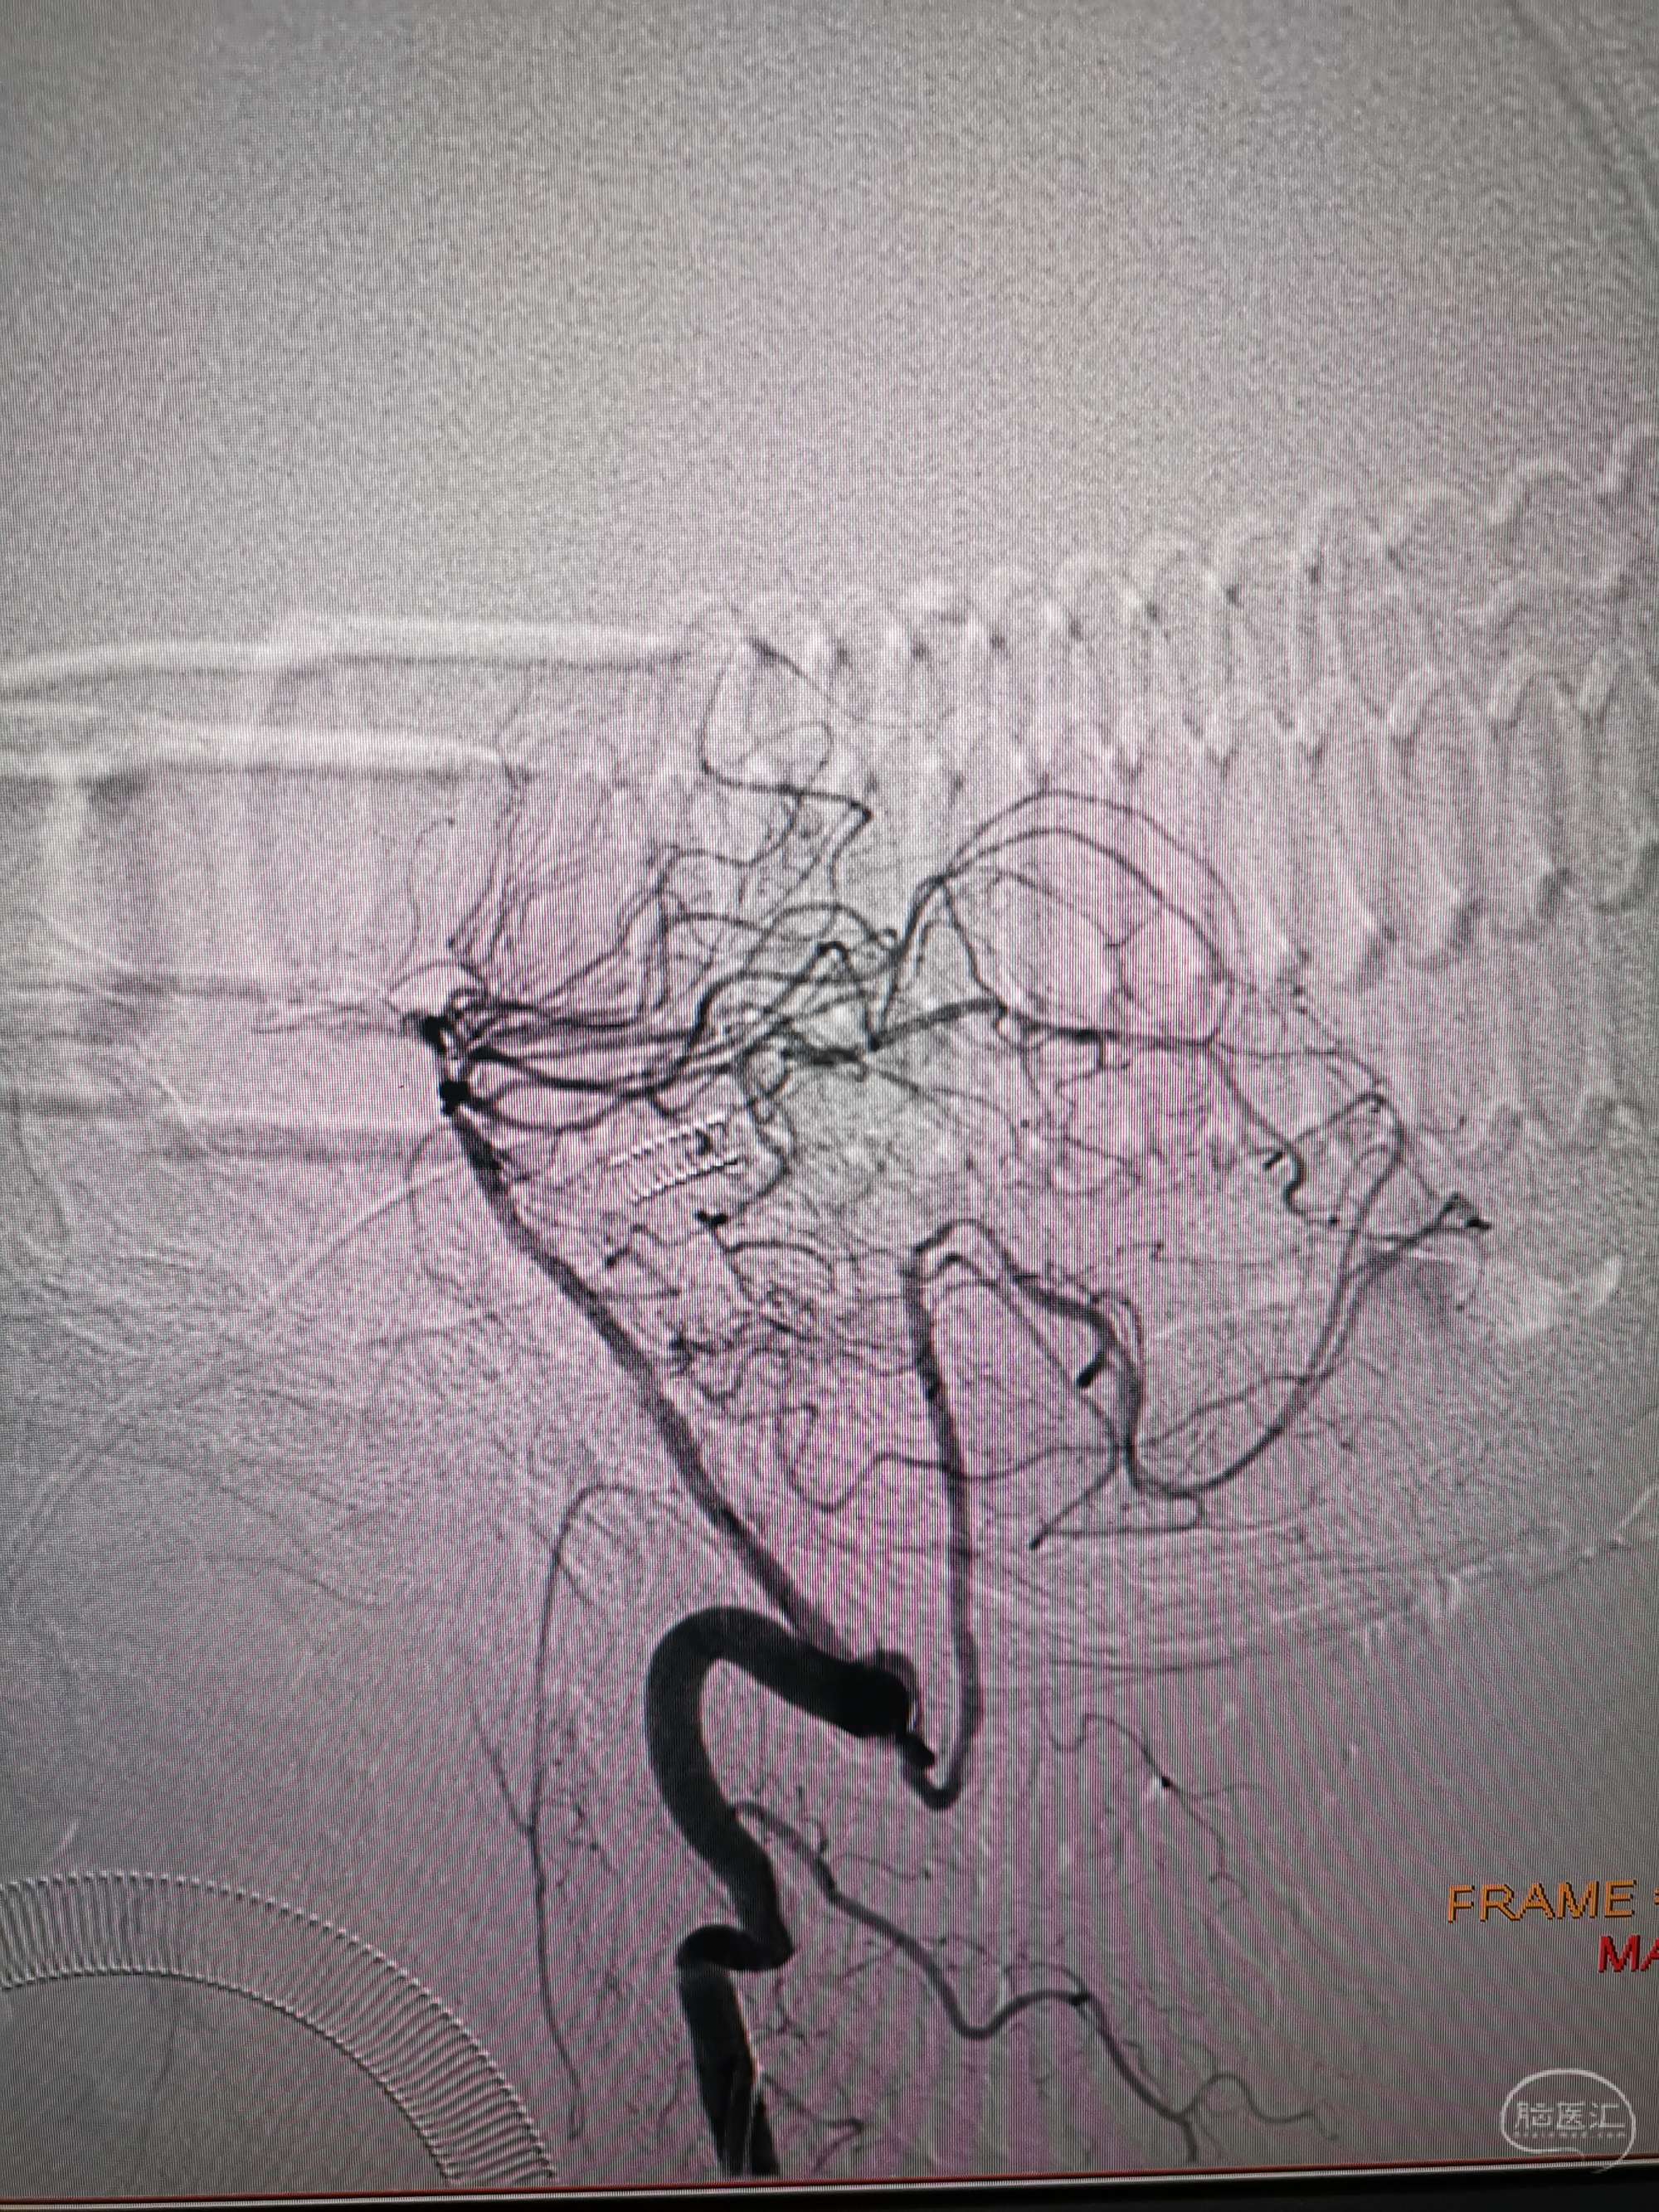

入院造影影像

男性,56岁,突发意识嗜睡,言语不能,吞咽困难,右侧肢体偏瘫于8月7日收住院。入院后急诊给予阿替普酶静脉溶栓,溶栓后造影显示双侧椎动脉闭塞,后交通未开放,仅右侧椎动脉有一穿支向基底动脉少量供血,考虑为原位狭窄后急性闭塞。核磁显示脑干及小脑多发急性梗死灶,拟双抗3周后行再通治疗。给予阿司匹林100mg及氯吡格雷75mg双抗3周后患者吸入性肺炎并反复消化道出血,停双抗治疗给予抗炎、抑酸药物治疗后感染控制,消化道出血停止,查血栓弹力图后重启双抗治疗一周,病情稳定,于今日在全麻下行左侧椎动脉再通术,手术顺利,详细情况如下